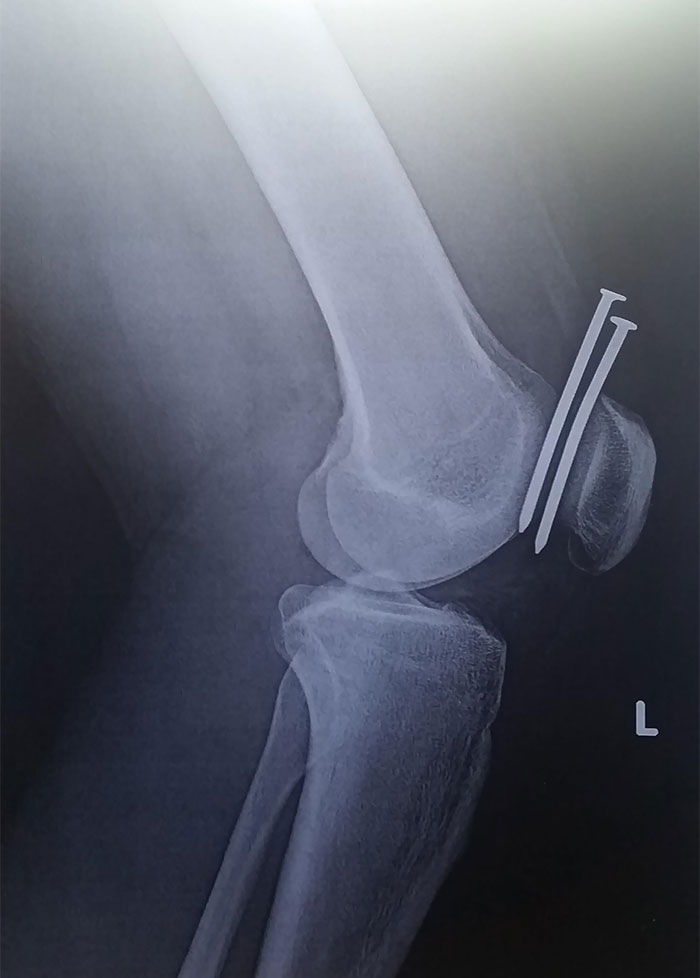

This Guy Had Two Nails From A Nail Gun Hit His Leg, And They Both Missed His Femur And His Kneecap

Ineffective Gold Thread Acupuncture Treatment For Osteoarthritis Of The Left Knee

Bullet In Knee After 14 Years. A 46-Year-Old Man With A Prior Gunshot Wound To The Left Knee Presented With Worsening Knee Pain

Radiographs showed fragmentation of the bullet into innumerable metallic particles